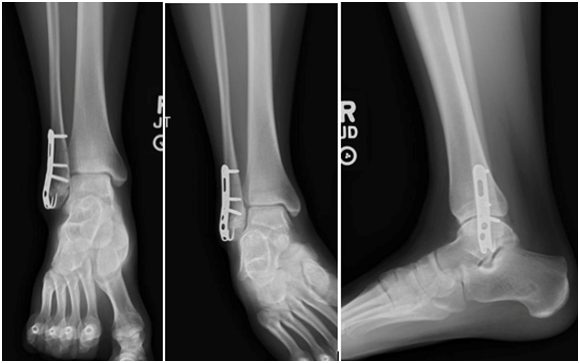

The patient is a 15-year-old skeletally mature female who sustained an inversion injury to her right ankle in January 2015, resulting in a Danis-Weber a fracture (Figure 1). The fracture was non-displaced, complete and intra-articular. At this time, she was seen by a partner of the attending author, placed in an immobilizing boot and allowed to bear weight. The patient was followed with serial radiographs. At 5 months, it was determined that the patient had a delayed union and was instructed to use a bone stimulator daily.

Figure 1 Initial radiographs. Anterior-posterior, Mortise and Lateral views of the right ankle. January 2015.